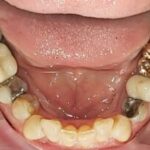

Verschiedene Metalle im Mund bilden galvanische Elemente und führen zur Korrosion

Raue Oberfläche, entstanden durch Korrosion!

Verschiedene Metalle im Mund. Hier Amalgam und eine Goldlegierung. Wie Sie nun wissen, sollten zwei unterschiedliche Metalle dringend vermieden werden.

Metalle unterliegen grundsätzlich der Korrosion (sie rosten), d. h. das Metallpartikel in den körpereigenen Organismus des Patienten gelangen und dort gespeichert werden können. Somit kann eine Erhöhung der toxischen Gesamtbelastung stattfinden